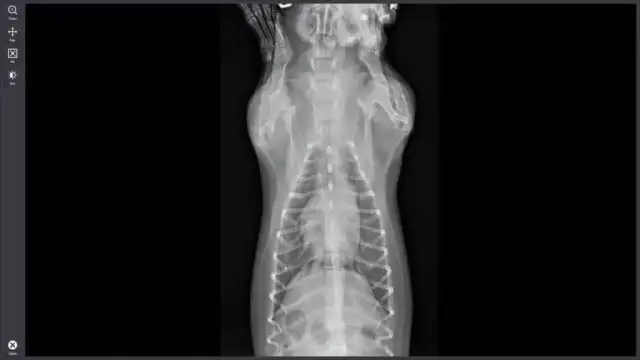

Ile kosztuje RTG zwierzęcia? Ceny badań weterynaryjnych 2024

Poznaj ceny RTG zwierząt w Polsce! Dowiedz się, od czego zależy koszt prześwietlenia i jakie są widełki cenowe. Sprawdź nasz przewodnik!